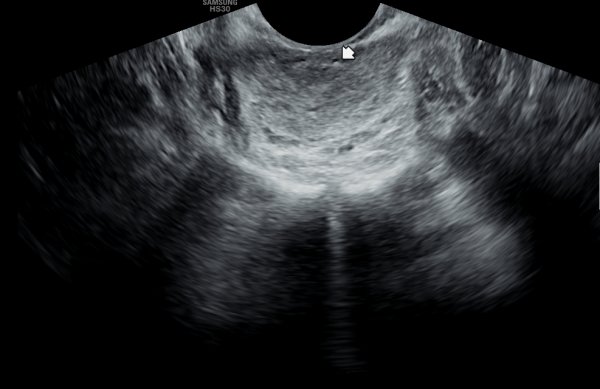

오래전부터 배뇨장애와 빈뇨 및 급박뇨등으로 다른 비뇨기과에서 약물 투여를 했으나 증상의 호전이 없다고 내원 당일 검사한 고환내 다량의 미석증이 관찰된 초음파 사진입니다.

This is an ultrasound image taken on the day of the patient’s visit, who reported long-standing urinary symptoms such as voiding difficulty, frequent urination, and urgency, with no improvement despite medication from other urology clinics. The scan shows a large amount of microcalcifications within the testes.

주2회 전립선의 표적 치료후 고환의 미석증이 줄어 들고 있는 경직장 전립선 초음파 검사 사진

Transrectal ultrasound image showing a reduction in testicular microlithiasis after twice-weekly targeted prostate treatment.

전립선의 표적치료후 고환의 미석증이 없어지고 고환이 커진 경직장 전립선 초음파 자료 입니다.(주2회 표적치료)

This is a transrectal ultrasound image showing the improvement after targeted prostate treatment.

After twice-weekly targeted treatment, testicular microlithiasis disappeared, and the testicles increased in size.

The ultrasound image on the left shows the initial examination, where testicular microlithiasis (tiny calcifications) was present.

The ultrasound image on the right is a follow-up study after several months of targeted therapy to the vas deferens, ejaculatory ducts, seminal vesicles, and prostate, twice a week.

The follow-up scan demonstrates that the previously noted microlithiasis has improved, suggesting that the targeted treatment contributed to the restoration of testicular health.

We hope this evidence may help inform colleagues and patients worldwide that such cases of testicular microcalcification, associated with chronic prostatitis or seminal tract obstruction, can improve through this approach.